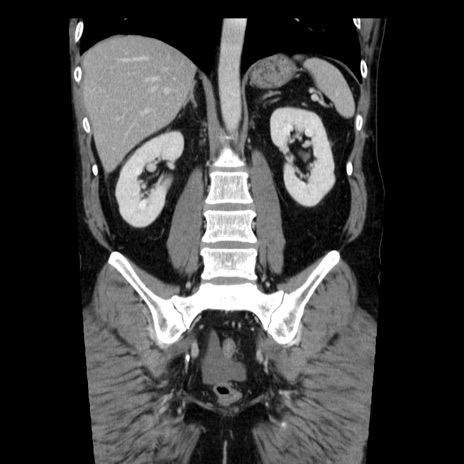

症例29(冠状断像)

【症例】40歳代男性

【現病歴】2日前から胃痛あり。徐々に周期的な激痛に変化した。本日になっても激痛があるため受診。

【身体所見】意識清明、BT 38-39℃台あり、腹部:膨満、やや硬、右下腹部に圧痛あり。

【データ】WBC 8500、CRP 23.26